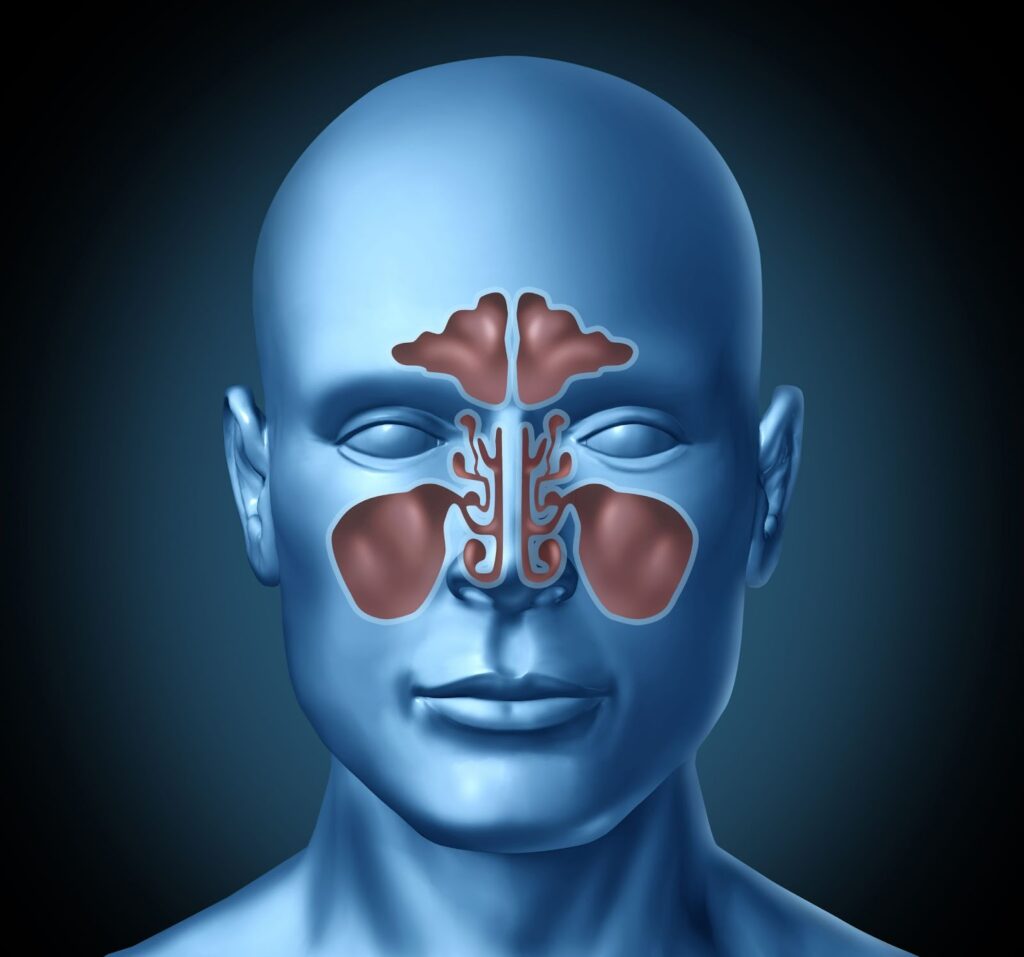

축농증은 주로 코 주위의 부비동이 염증을 일으켜 고름이 고이는 상태를 지칭합니다. 이 질환은 부비동염(sinusitis)이라고 하며, 코 주위의 빈 공간인 부비동이 염증으로 인해 기능이 떨어지면서 발생합니다. 이 질환은 급성과 만성으로 나뉘며, 급성 부비동염은 보통 1개월 이내에 증상이 발생하는 반면, 만성 부비동염은 3개월 이상 지속됩니다.

5. 축농증 진단과정 및 검사방법

축농증의 진단 과정은 다음과 같습니다.

- 신체검사 : 코 내부를 확인하기 위해 비경(Context: endoscope) 또는 비인두 내시경을 사용합니다.

- 영상 검사 : 필요에 따라 X-선 검사 또는 CT 촬영을 통해 부비동의 상태를 확인합니다.